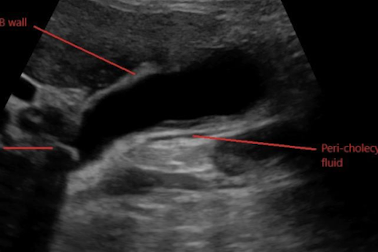

What is this and what type of scan

Cholecystitis, US